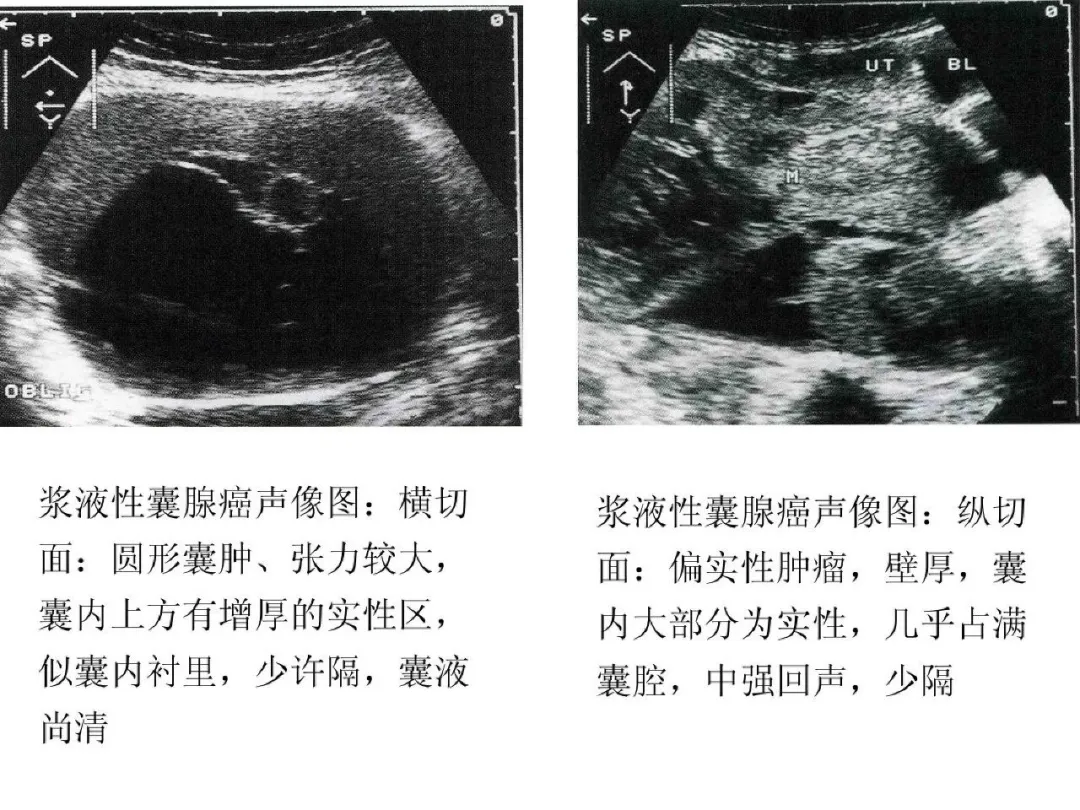

浆液性囊腺癌

●是临床上最常见的卵巢恶性肿瘤,约占卵巢恶性肿瘤的40%-60%,半数为双侧,乳头可穿过瘤壁向外生长。

●二维超声图特征:呈圆形或椭圆形,表面光滑或不规则;囊壁厚;多显示囊实性,囊液清亮或混浊,内壁有毛刷状小乳头,强回声粗大乳头,实质部分呈强回声或低回声;血流较丰富;多伴有腹水。